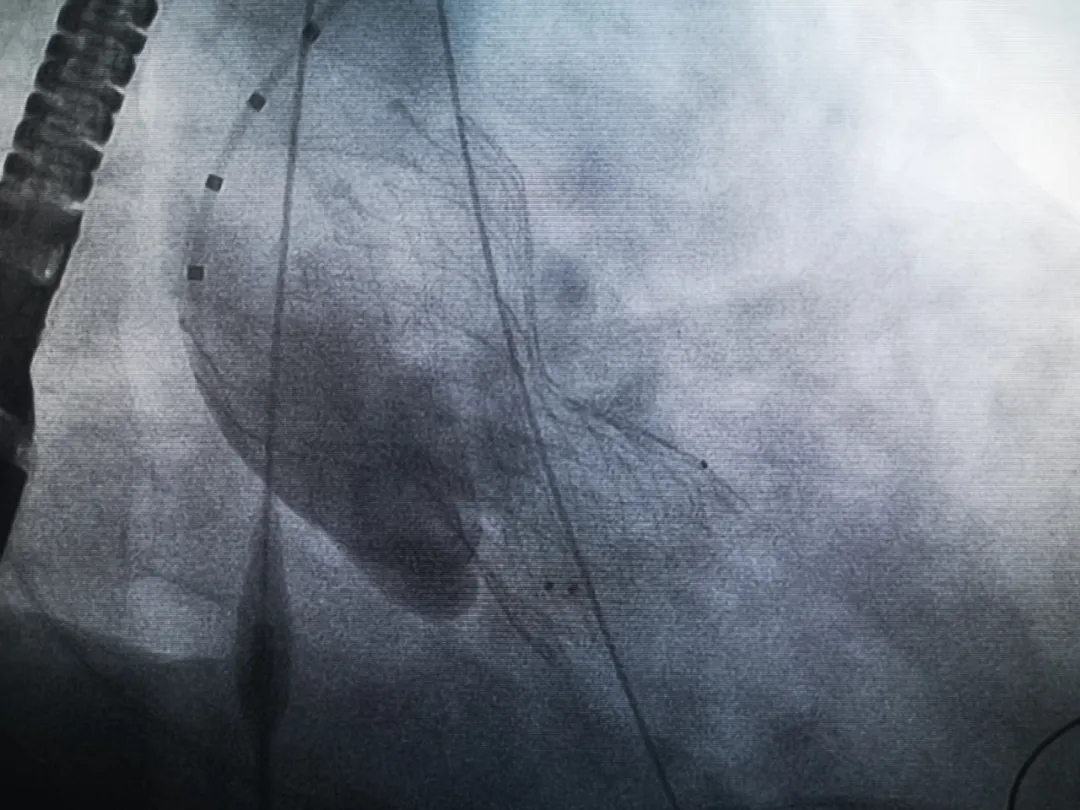

手術(shù)過程緊張而有序,心臟沒有停跳,也沒有太大的血壓波動;球囊擴(kuò)張的恰到好處,瓣膜釋放之后超聲醫(yī)生的評估是至關(guān)重要的,因為我們提前就準(zhǔn)備了后擴(kuò)張,也準(zhǔn)備了瓣中瓣,甚至還準(zhǔn)備了瓣周漏封堵。所幸的是,超聲診療中心劉夢梅醫(yī)生說:沒有返流、沒有瓣周漏,瓣膜形態(tài)良好,跨瓣壓差約17mmHg(相較于術(shù)前的87mmHg還是可以接受的)。瓣膜置入的成功并不是慶祝的時候,從戰(zhàn)場撤退仍然需要謹(jǐn)慎。由于王子特別胖,腹股溝區(qū)脂肪尤為肥厚,在股動脈插管拔除、確認(rèn)搏動正常之后,便逐層縫合。同時為了美觀、縫合之后不至于鼓個包出來,我們又仔細(xì)剪除了部分脂肪。術(shù)后次日,王子便可以下床活動了。